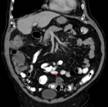

https://commons.wikimedia.org/wiki/File:03-Sigmadivertikulitis_CT_cor_001_Kleiner_Abszess.png

Description Deutsch: Sigmadivertikulitis in der Computertomographie (coronar rekonstruiert).

Perforation mit kleinem Abszess.